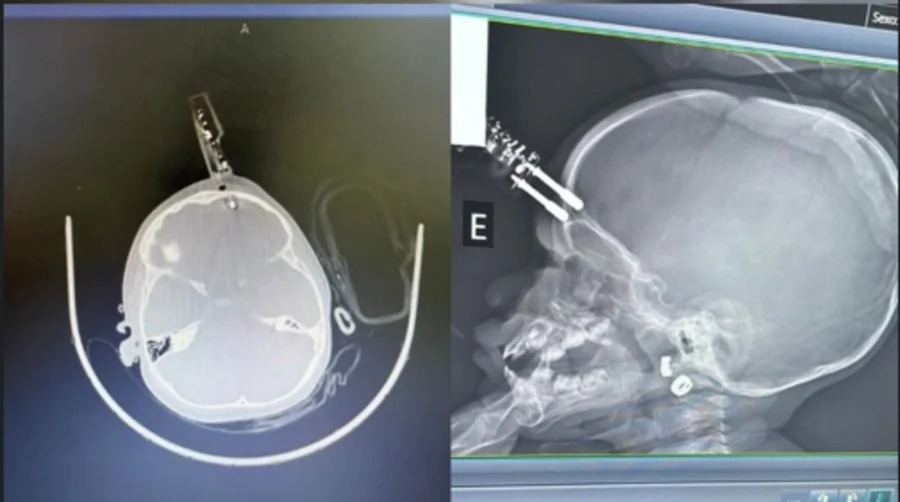

Uma bebê de 1 ano e 4 meses sofreu um grave acidente doméstico em Divinópolis, Minas Gerais, após cair da cama enquanto segurava um carregador de celular. Com a queda, o objeto acabou ficando cravado na testa da criança.

A criança foi levada às pressas para uma unidade hospitalar da cidade, onde passou por procedimento cirúrgico para a retirada do carregador e limpeza do ferimento. A equipe médica informou que a intervenção ocorreu sem complicações.

Após permanecer em observação, a bebê apresentou boa evolução clínica e recebeu alta médica. De acordo com os profissionais de saúde, não foram constatados danos neurológicos até o momento.